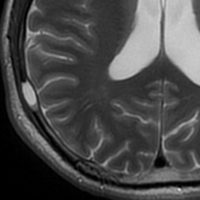

9歳の男の子です。右側頭部が腫れてきたのに気づきました。頭蓋骨のいびつな破壊像があります。

左はMRI T2強調画像です。まるで丸い腫瘍のように見えます。

下のT1強調画像では,ガドリニウム造影剤で強く増強されていて皮下に炎症性腫脹がみられ,活動期の病変であるのがわかります。

この病変は単発(孤発)病変ですが,ややいびつな形をしていて,頭皮の方に盛り上がっていますから,活動性の病変です。手術で完全摘出すると治りますから,骨欠損が広がるようなら手術したほうがいいです。理由は,手術が簡単なこと,病理診断がつくこと,これ以上の病変の広がりを抑えることです。最近は自然の骨に近いような人工骨で補填することができますが,骨形成しなくても自然修復で骨形成されます。とくに,低年齢児では骨形成をしない時もあります,頭蓋骨が自然再生するからです。